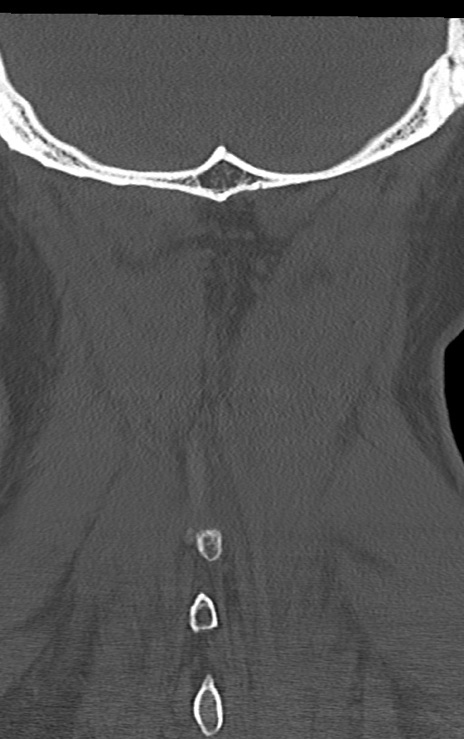

頚椎CT

矢状断像